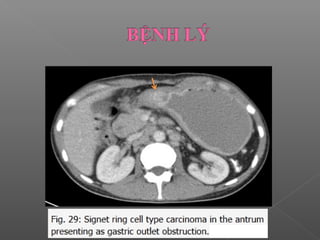

 Ung thư dạ dày

Ung thư phổ biết nhất là ung thư biểu mô tuyến

 Ung thư biểu mô tuyến

Phổ biến nhất, hay gặp là ung thư tuyến nhầy.

CT: khối có bờ không đều hoặc thành dạ dày dày lan

tỏa không đều

 Ung thưbiểu mô tuyến Phổ biến nhất, hay gặp là ung thư tuyến nhầy. CT: khối có bờ không đều hoặc thành dạ dày dày lan tỏa không đều